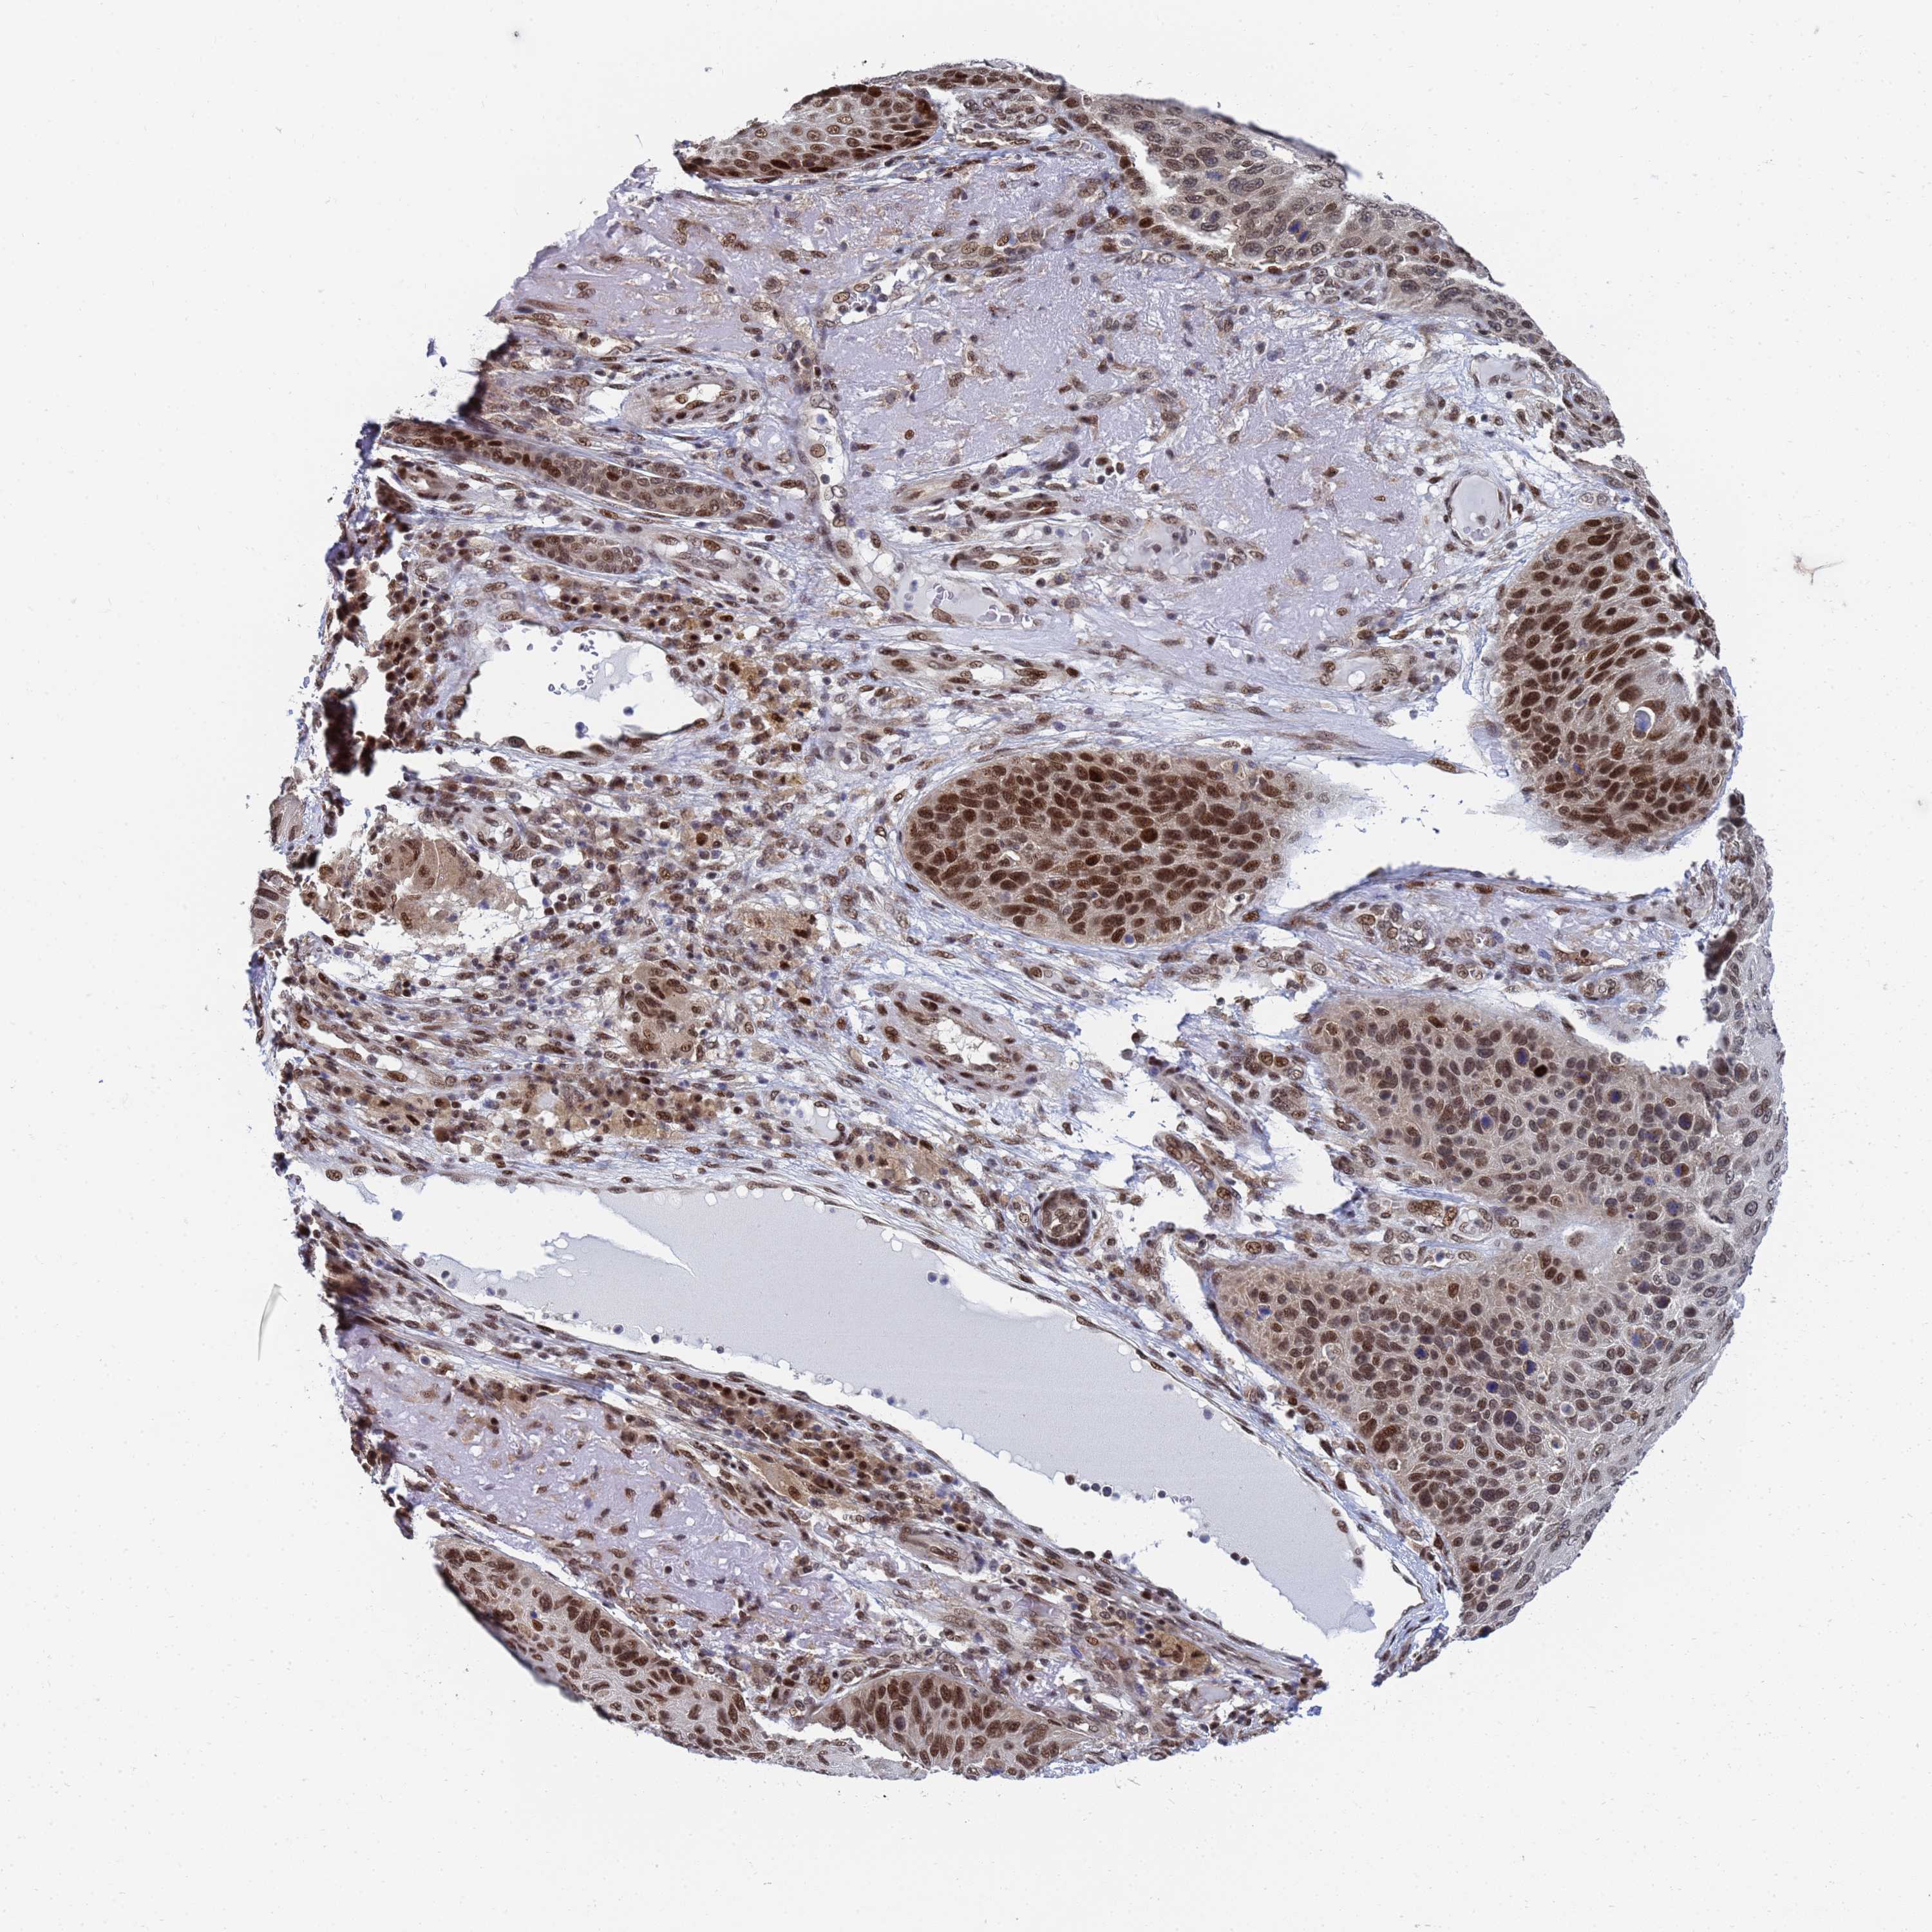

SKIN CANCER - Protein expressioni

A mouse-over function shows sample information and annotation data. Click on an image to view it in a full screen mode. Samples can be filtered based on level of antibody staining by selecting one or several of the following categories: high, medium, low and not detected. The assay and annotation is described here.

Each image is clickable and will lead to virtual microscopy that enables deeper exploration of all samples and also displays staining intensity scores, fraction scores and subcellular localization as well as patient and tissue information for each sample.

Antibody HPA035693

Staining

High

Intensity

Strong

Quantity

>75%

Location

Nuclear

Basal cell carcinoma